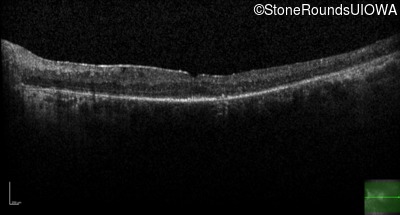

Age at visit: 23 years

Age at visit: 24 years